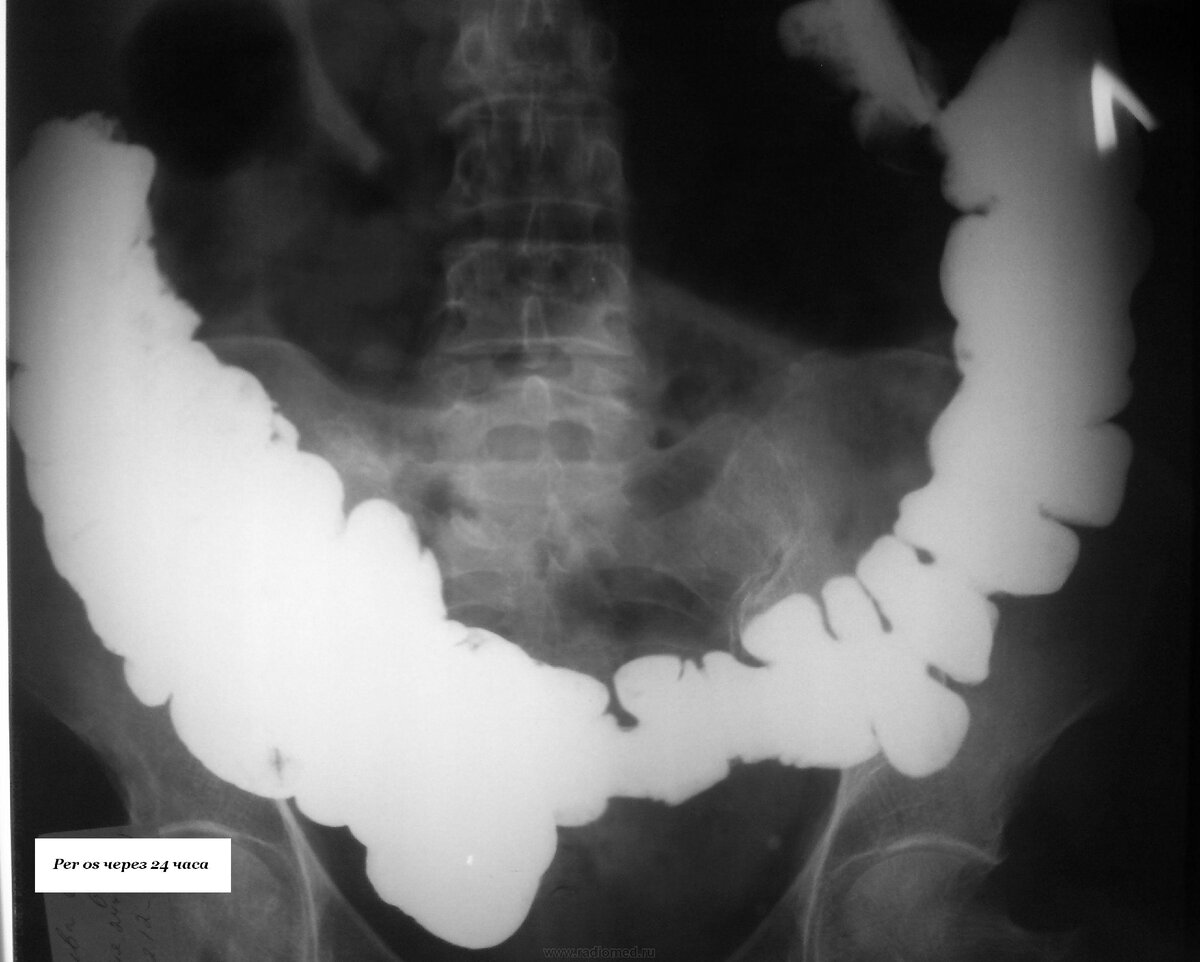

Острая кишечная непроходимость - это состояние, при котором происходит частичное или полное прекращение продвижения содержимого через кишечник. Это может вызвать серьёзные осложнения, включая перфорацию кишечника, перитонит и сепсис.

Опухоли могут перекрывать просвет кишечника, затрудняя прохождение содержимого.

Заворот кишок (Volvulus) - закручивание кишечника вокруг его мезентерии, что нарушает кровоснабжение.